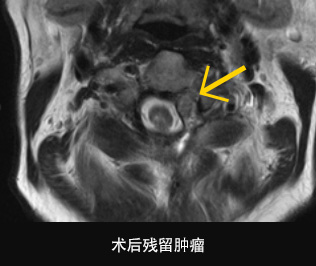

[没有能够通过手术完全切除脊髓肿瘤时]

已有报告指出,对于颅底脊索瘤或软骨肉瘤患者,当无法进行手术或在术后有肿瘤残留时,能够利用质子治疗方式在不会导致副作用的状态下提升放射线剂量,从而提升肿瘤的控制率。